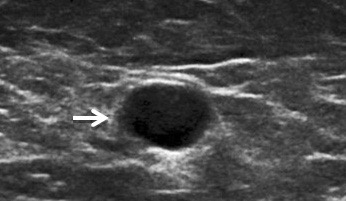

A PET scan gives my physicians a clear view of any new cancer activity. The thought gives me chills, and left me nauseated with fear the day before my scan, which was only days ago.

Preparation for a PET scan involves spending the day before the test as leisurely as possible, since muscle activity can light up on the study, giving a false positive. I was told to drink a lot of water, but not to have anything to eat or drink after midnight.

Once there, an IV is inserted, before the technician is called. She arrives with an ominous looking metal box containing a syringe of a radioactive material which she injects into my vein, while we chat, as if there is nothing at all strange about this.

I have no reaction to the substance, and I read for the hour it takes for it to circulate through my body. I try not to think about that, assured that its half life is only ninety minutes, so I will soon be rid of it.

The scanner is in a room that is quite cold, so I’m bundled up with blankets, and quite comfortably bolstered with a leg rest and a pillow, before the study starts. There is nothing uncomfortable about the exam, no claustrophobic tunnels, no knocking noises, not even a computerized voice filling the room. The only instruction I am given is not to move, and I do not move, for if movement prolongs this experience, I will be the most unmoving patient of the day.

Results: Waiting for the results, is far more stressful than the actual scan. When I am told the test is negative, the relief is phenomenal, and I am grateful.